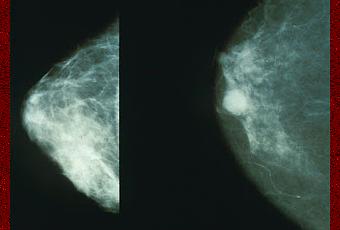

Mammographie montrant un cancer du sein à droite.

Source iconographique et légendaire: https://fr.wikipedia.org/wiki/Cancer_du_sein